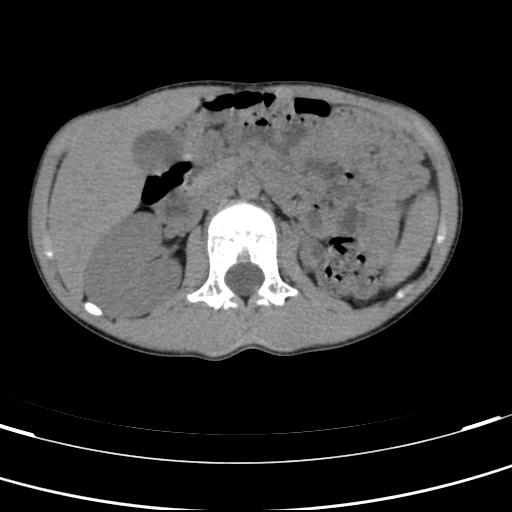

标题: PED3157:左肾缺如,请教脾脏的改变?、、

男孩,9岁。胃部不适。

脾脏变异,左肾未见,游走、异位、发育不全都要可能,增强或ivp造影。

脾脏位于左侧,但数个脾脏呈分离状态,左肾缺如,右肾代偿肥大。考虑多脾综合征。